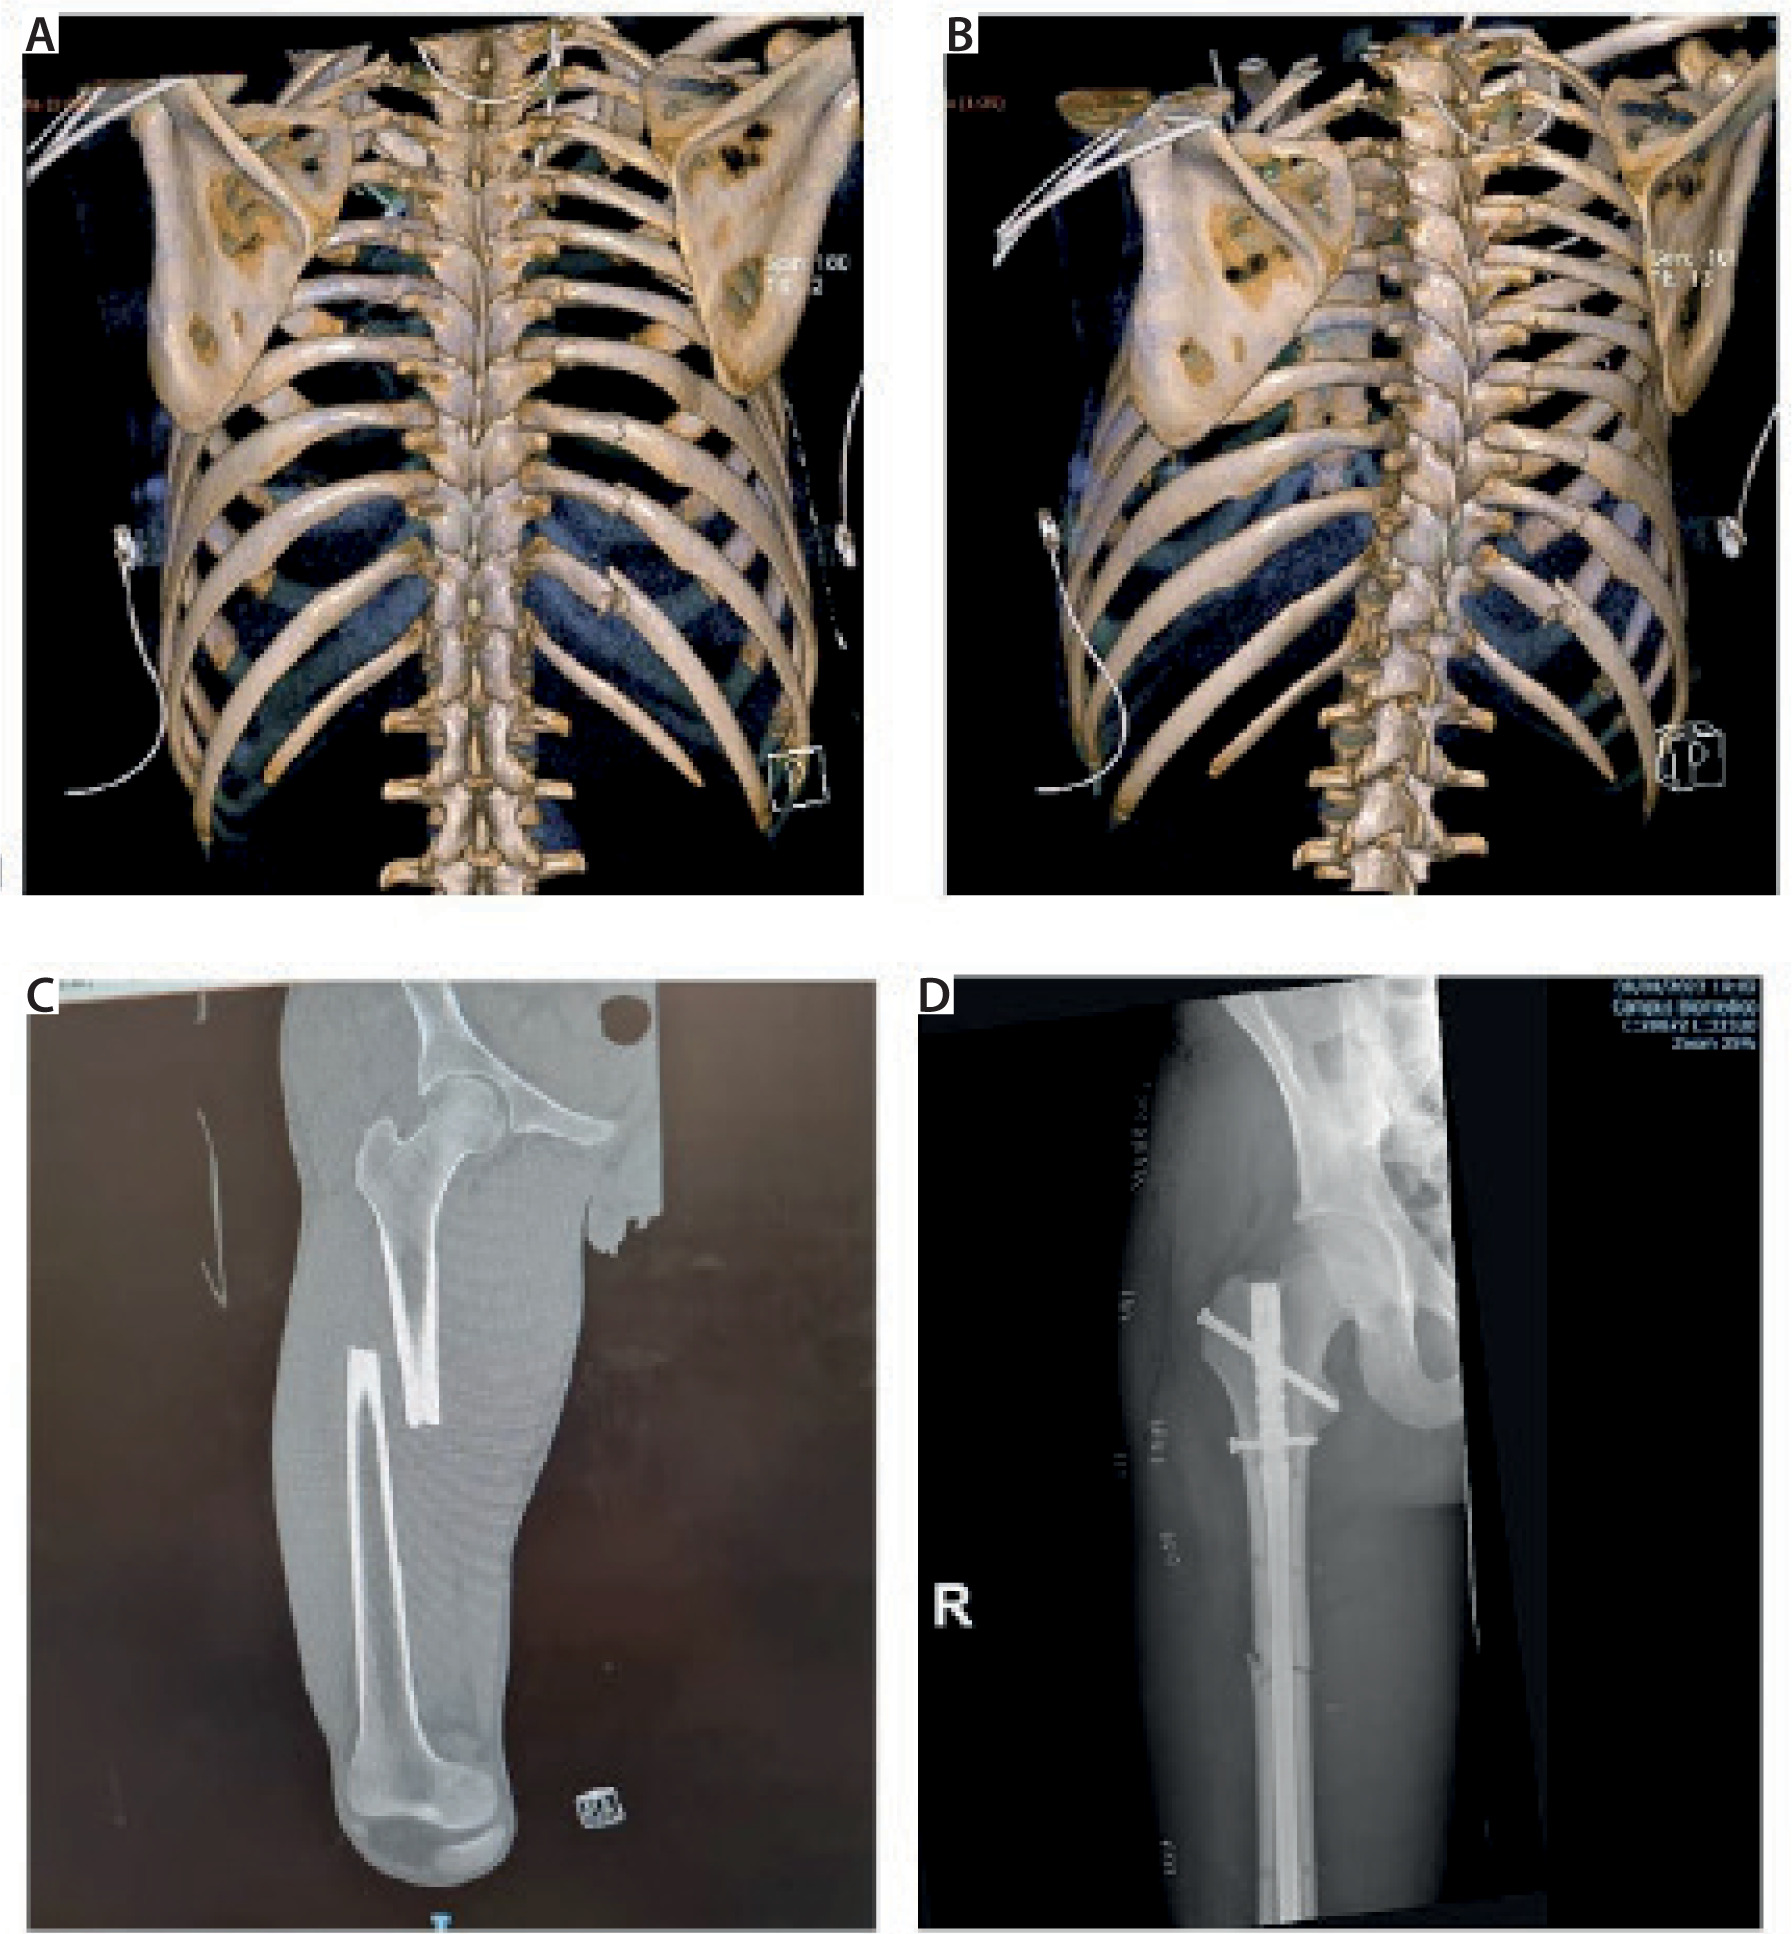

The initial computed tomography (CT) scan revealed: a severe pneumomediastinum; a large right-sided pneumothorax with partial collapse of the lung, small pneumothorax on the left in the apical and anterosuperior region; multiple rib fractures bilaterally, specifically ribs I, II, III, and IV on the left and ribs II, III, IV, VI, VII, and XII on the right (Figures 1A and 1B); fracture of the upper third of the right scapula and right sternoclavicular subluxation; a hepatic subcapsular hematoma at segment VI (approximately 13 × 6 mm); evidence of suspected right renal hematoma; a compound fracture of the left transverse process (Th1); and a fracture of the middle third of the right femoral diaphysis (Figure 1C).

FIGURE 1

A, B) 3D chestcomputed tomography reconstruction with 2 perspectives showing posterior rib fractures. C, D) X-ray of femur fracture on admission to the emergency room and after surgical reduction (one week later)

Eight days after hospital admission, he underwent femur fracture fixation through the placement of an intramedullary rod (Figure 1D). Regional anesthesia was performed for both anesthetic and analgesic purposes. The patient was premedicated with 0.1 mg of fentanyl i.v. and received the following ultrasound-guided blocks: FNB and subgluteal sciatic nerve block, both using a mixture of 0.75% ropivacaine and 2% mepivacaine in 10 mL doses, as well as ONB with 5 mL of the same mixture. Additionally, an SAP block was administered at the fourth intercostal space using 20 mL of ropivacaine 0.25%. The patient underwent the procedure in a supine position on a rigid traction table, which caused significant pain before the block (NRS score of 8) but was noted to be significantly less painful following the block (NRS score of 2). Throughout the surgery, the patient was under deep sedation with a continuous intravenous infusion of propofol and maintained spontaneous breathing using a Venturi mask (FiO2 0.5).